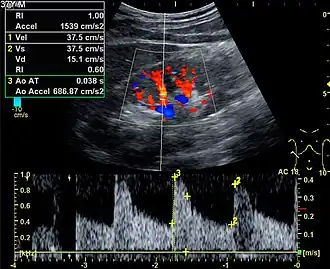

![]() Doppler ultrasound (US) of a normal adult kidney with the estimation of the systolic velocity (Vs), the diastolic velocity (Vd), acceleration time (AoAT), systolic acceleration (Ao Accel) and resistive index (RI). Red and blue colors in the color box represent flow towards and away from the transducer, respectively. The specrogram below the B-mode image shows flow velocity (m/s) against time (s) obtained within the range gate. The small flash icons on the spectrogram represent initiation of the flow measurement.[1] | |

Doppler ultrasonography of the kidney is widely used, and the vessels are easily depicted by the color Doppler technique in order to evaluate perfusion. Applying spectral Doppler to the renal artery and selected interlobular arteries, peak systolic velocities, resistive index, and acceleration curves can be estimated (Figure 4) (e.g., peak systolic velocity of the renal artery above 180 cm/s is a predictor of renal artery stenosis of more than 60%, and a resistive index, which is a calculated from peak systolic and end systolic velocity, above 0.70 is indicative of abnormal renovascular resistance).[1]